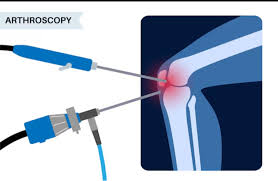

Joint Surgery FAQs in Nagpur | Dr. Abhishek Bhalotia at …

Outpatient Arthroscopy Benefits in Nagpur | Dr. Abhishek Bhalotia at …